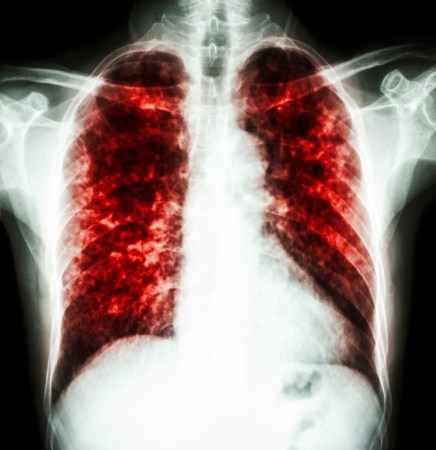

Lactobacillus bacteria, such as those shown here — colored purple to show up against the background tissue — can be tweaked to hunt down and poison disease-causing germs. Think of them as little antibiotic factories.

Eraxion/ iStockphoto

With that in mind, Collins’ team started a new line of experiments. They work with Lactobacillus (LAK-toh-bah-SILL-us). It is the type of good bacteria found in yogurt. Inside the human gut, these helpful bacteria can fight infections.

Collins’ group wants to re-engineer the genes in Lactobacillus. This new breed of bacteria would be able to sense when disease-causing bacteria are nearby. Then it would produce a toxic substance, one tailored to kill only one particular invader. For instance, this tweaked microbe might scout for — and attack — the bacterium responsible for cholera. Its infection causes life-threatening diarrhea.